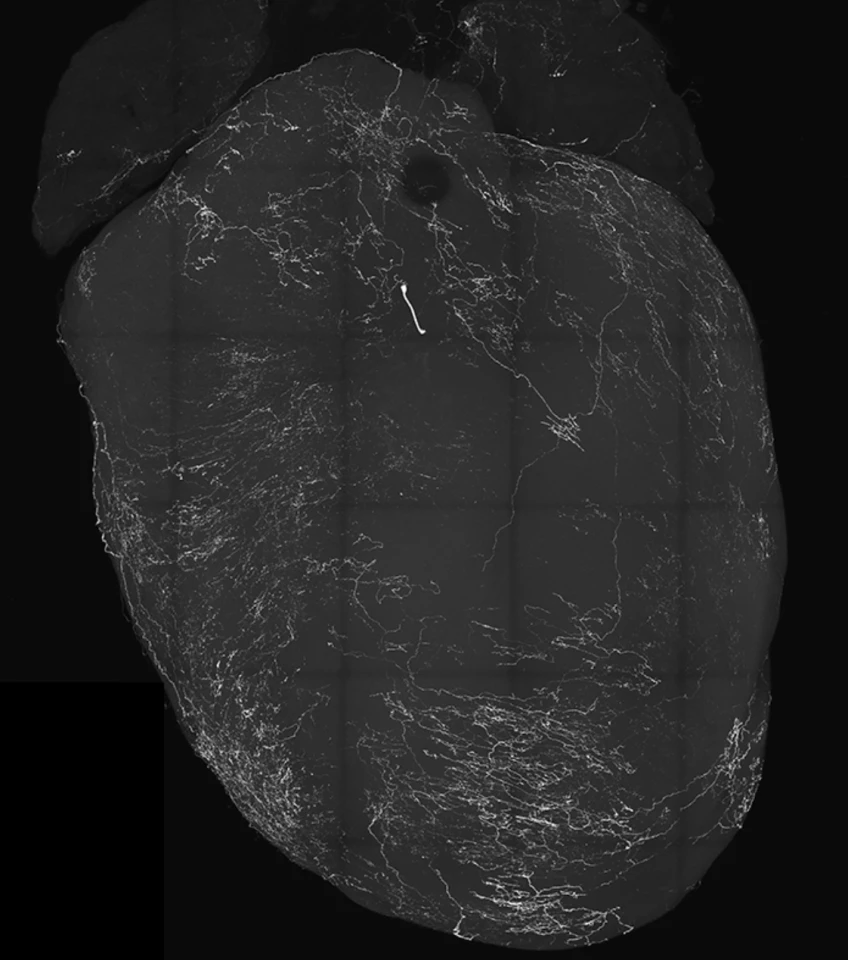

The study was published in the journal Nature, and the video below captures the heart-brain "crosstalk", as heart activity slows in response to the stimulation of VSNs, which trigger fainting.